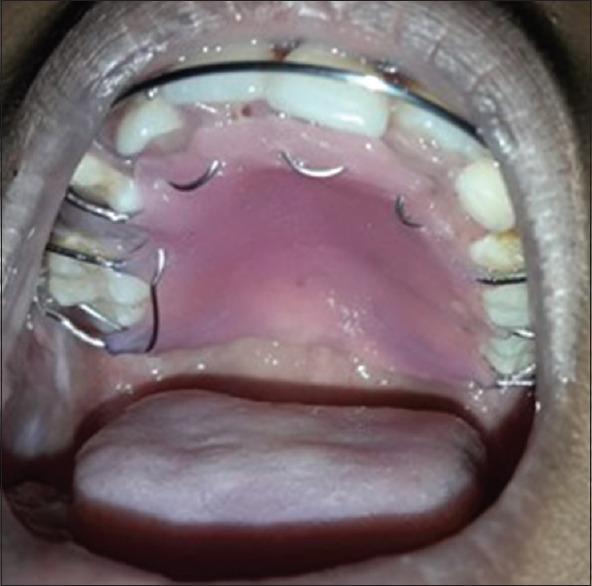

Myoepitheliomas (MEs) are extremely rare benign neoplasms composed of ectodermally derived contractile smooth muscle cells (myoepithelial cells). Various tissues such as the salivary glands, breast, larynx, and sweat glands show the presence of these myoepithelial cells. They occur, principally, in the parotid gland and infrequently in minor salivary glands. The term "Myoepitheliomas" was first coined by Sheldon in 1943. It is an uncommon salivary gland tumor which accounts for < 1% of all major and minor salivary gland tumors. Batasakis considers the ME to be "one-sided" variant at the opposite end of the spectrum from the pleomorphic adenoma. There are distinct histological and immunohistochemical characteristics of the tumor which aid in the diagnosis. ME of the palate is uncommon, and only a limited number of cases have been reported in the English literature. It shows a benign clinical course with recurrence in up to 20% of cases without metastasis. The present article sheds light on the presence of ME of minor salivary glands in the palate of 9-year-old child.

肌上皮瘤(MEs)是一种极其罕见的良性肿瘤,由外胚层来源的收缩性平滑肌细胞(肌上皮细胞)组成。唾液腺、乳腺、喉和汗腺等各种组织中都存在这些肌上皮细胞。它们主要发生在腮腺,很少发生在小唾液腺。“肌上皮瘤”一词最早由谢尔登于1943年提出。它是一种不常见的唾液腺肿瘤,占所有大、小唾液腺肿瘤的比例不到1%。巴塔萨基斯认为肌上皮瘤是多形性腺瘤谱系另一端的“单侧”变体。该肿瘤具有独特的组织学和免疫组化特征,有助于诊断。腭部肌上皮瘤并不常见,英文文献中仅报道了少数病例。它表现为良性临床病程,高达20%的病例会复发,但无转移。本文揭示了一名9岁儿童腭部小唾液腺肌上皮瘤的存在情况。